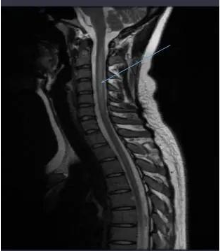

家人还以为她得到了什么疾病,连忙送到医院检查,被诊断为“脊髓亚急性联合变性”,是体内严重缺乏维生素B12导致。然而,这种疾病多数出现中老年人身上,鲜见年轻人,除非受外部物质影响。

二是笑气会通过不可逆氧化维生素B12的钴中心成为其他钴胺素类似物,排出体外,引起维生素B12失活且缺乏,导致脊髓亚急性联合变性,出现四肢麻木无力,站立不稳,经常性跌倒,不能动弹等间歇性症状。

维生素B12不同于其它维生素,人体内获得维生素B12很大一部分是靠人类肠道细菌提供,而长期吸食笑气的患者导致的维生素B12合成几乎为零,如果不及时治疗,最终就会致使滥用者瘫痪,重新站起来的几率非常渺茫。